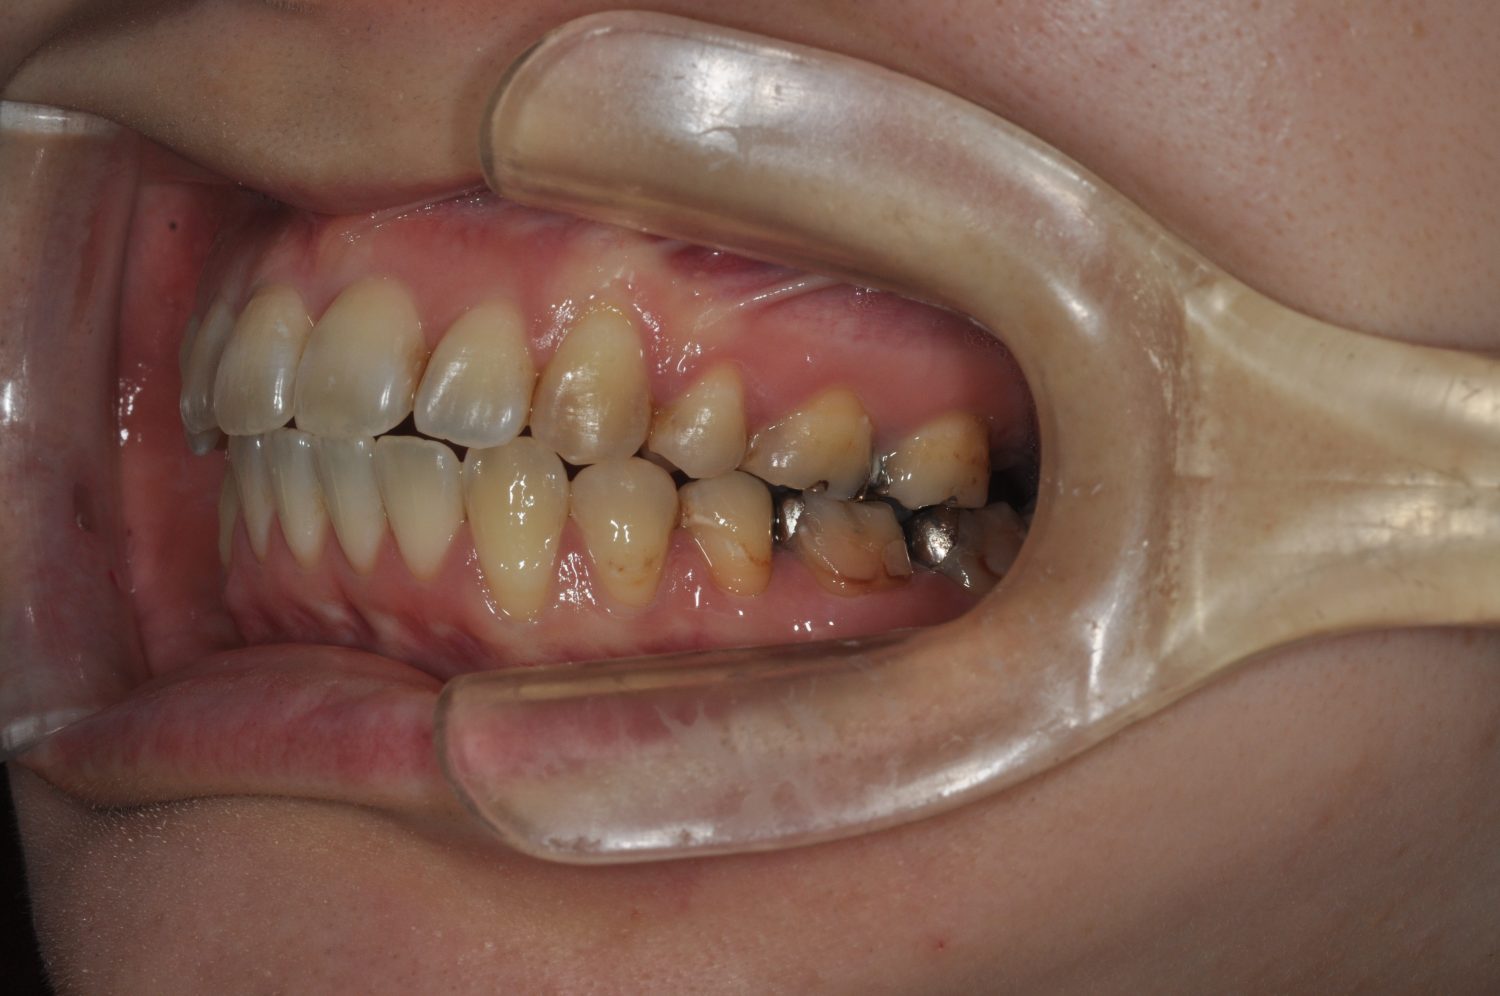

| 主訴 | 前歯の出っ歯を直したい |

| 治療内容 | 上下顎とも標準範囲であるが、上下顎前歯ともに唇側傾斜による、上下顎前突。上顎小臼歯を抜去し配列を行うこととした。 |

| 治療費 | Ⅱ期治療費:770,000円 (税込) 調整料 5,500円 (税込)×23回 保定時:22,000円 (税込) 計 918,500円 (税込) |

| 治療期間 | 2年1ヶ月 |

| 治療回数 | 25回 |

| 想定されたリスク | 矯正器具の装着に伴い、むし歯や歯周病のリスクがありました。また、歯根吸収や歯肉退縮のリスクもありました。 |

上下顎前歯の唇側傾斜による上下顎前突。オーバージェットが大きいため、上顎のみの抜歯で配列を行った。